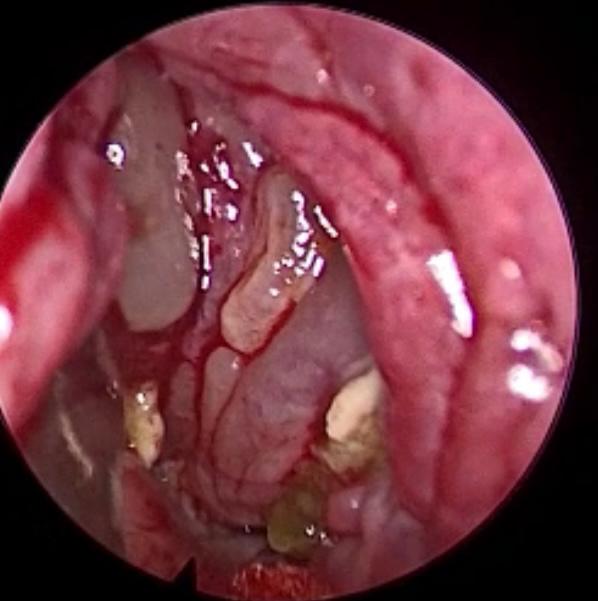

وأضاف الدكتور الحياري : بعد الفحص السريري والتنظير ، والفحص الشعاعي متعدد الجوانب ، تبين وجود التهابات على شكل تكتلات ، في جميع الجيوب الأنفية للجهة اليسرى ، من الوجهة مع وجود علامات لاحتماليه التهابات فطريه ، وبناء عليه تم ادخال المريض إلى غرفه العمليات.

وقال د. الحياري : مع تقدم العلم أصبح هنالك طرق حديثة لعلاج التهابات الجيوب الأنفية المزمنة ، وذلك عن طريق استخدام المنظار ، حيث تكون الرؤيا أوضح لطبيب الجراح والوصول للأماكن البعيدة في قاع الجمجمة ، بشكل اسهل وأدق وبدون حدوث أي مضاعفات للمريض.

وتابع قائلا : لقد تم استخدام المنظار مع اجهزه خاصه ، لتنظيف الجيوب حيث تم الدخول عليها ، وتنظيفها من الالتهابات الفطرية المتراكمة بدقه ، وبدون اي ايذاء للعين وقاع الجمجمة.

وأضاف د. الحياري : إن نسبة نجاح هذا النوع من العمليات يكمن في التطور الحديث في المنظار ، وذلك بسبب الرؤيا الأوضح وسهولة الوصول إلى الأماكن البعيدة في منطقه الجيوب ، مع الخبرة العملية للطبيب الجراح ، يجعل نسبة نجاح هذه العملية كبيرة جدا وقد تفوق هذا النوع من العمليات( ٩٠% ).